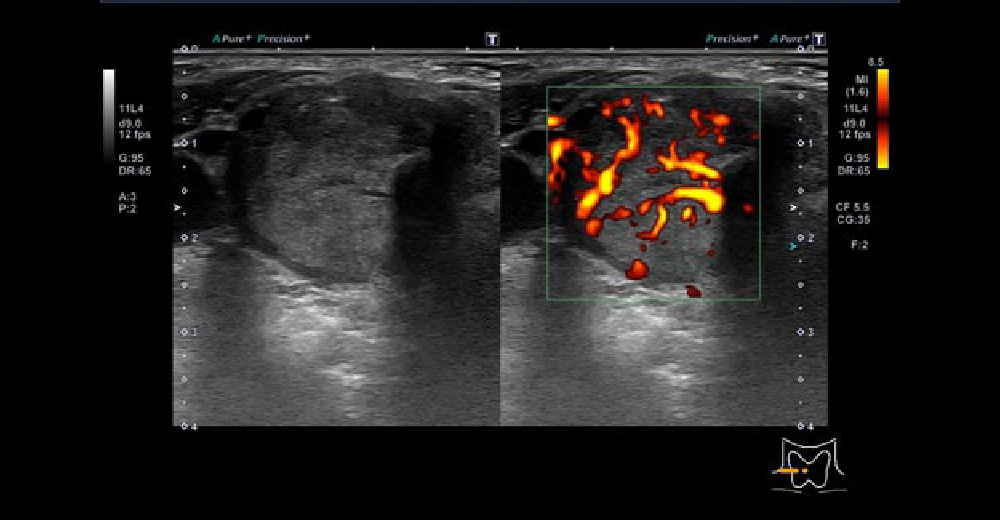

甲状腺右葉に境界不整、辺縁不整、内部不均一で一部石灰化を伴い、長径30mm程度の内部血流を伴う腫瘤を認めます。甲状腺全摘に至りました。

甲状腺乳頭がん 甲状腺乳頭がん